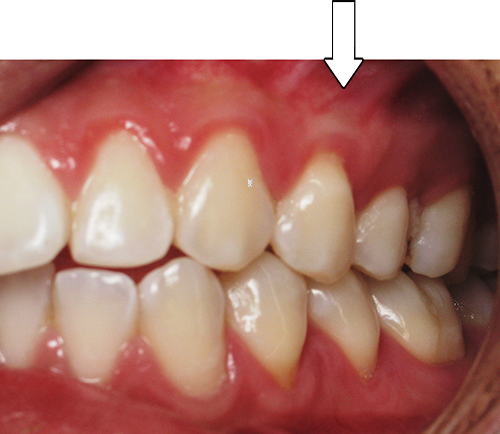

Smile Gallery

After Series of Teeth Extractions, Upper Left Canine Unerupted.

Ready to Start Ortho Treatment